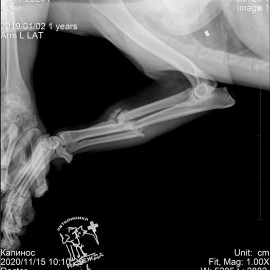

Рентгенологический снимок после проведенной операции.

Жалобы на хромоту на переднюю лапу в течение 3-х недель после перенесенной травмы. После проведенных исследований собаке был поставлен диагноз - застарелый перелом костей левого предплечья. Кости стали срастаться неправильно. Проведена операция - корригирующий остеосинтез костей левого предплечья.